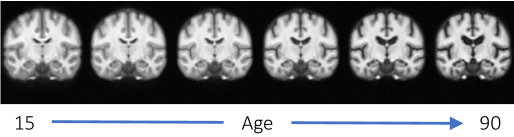

In this work, we present AtlasMorph, a learning strategy to generate conditional templates and corresponding anatomical label maps as a function of subject attributes. While we believe the strategy is general, in this paper we demonstrate it only on brain anatomy. Our method can leverage all the data available when constructing templates. There is no need to train a different network on a subset of the data for each combination of attributes. Figure 1 shows examples of templates, generated on demand by sampling our trained age-conditioned template function. Our framework can also adjust when label maps or subject attributes are missing.

Figures 5 and 6 show visualizations for templates produced by AtlasMorph and the AtlasMorph-Uncond variants. Supplemental Figure 15, and Figure 16 show templates optimized using ANTs. The Aladdin templates are shown in Supplementary Figure 17 and Figure 18. The learned AtlasMorph templates are significantly sharper than the average of the population, shown in Figure 4.

Conditional AtlasMorph captures variability across age that a single unconditional template cannot. For example, younger subjects have more grey matter, and ventricles get larger as subjects grow older. The intensities of the atlas involve contrast changes that are consistent with segmentation boundaries, capturing the alignment between the intensity templates and the segmentation templates. We include additional visualizations of templates conditioned on age, sex and disease (cognitively normal - mild cognitive impairment - Alzheimer’s disease) in the Supplemental Material, Figure 21.